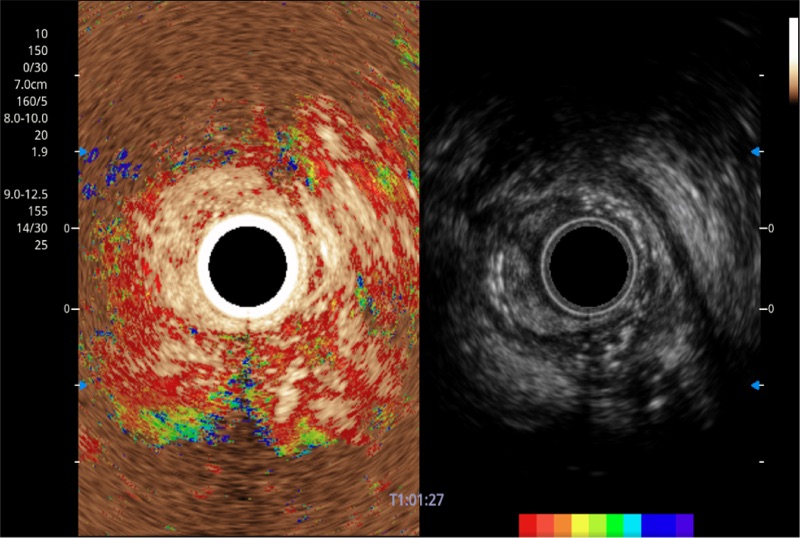

可人为将灰阶图像转变成彩色的显示方式,增强人眼对于不同回声强度的敏感度,主观上增加了图像分辨率

具有四种造影成像效果

清晰显示胆总管及周围血管分布